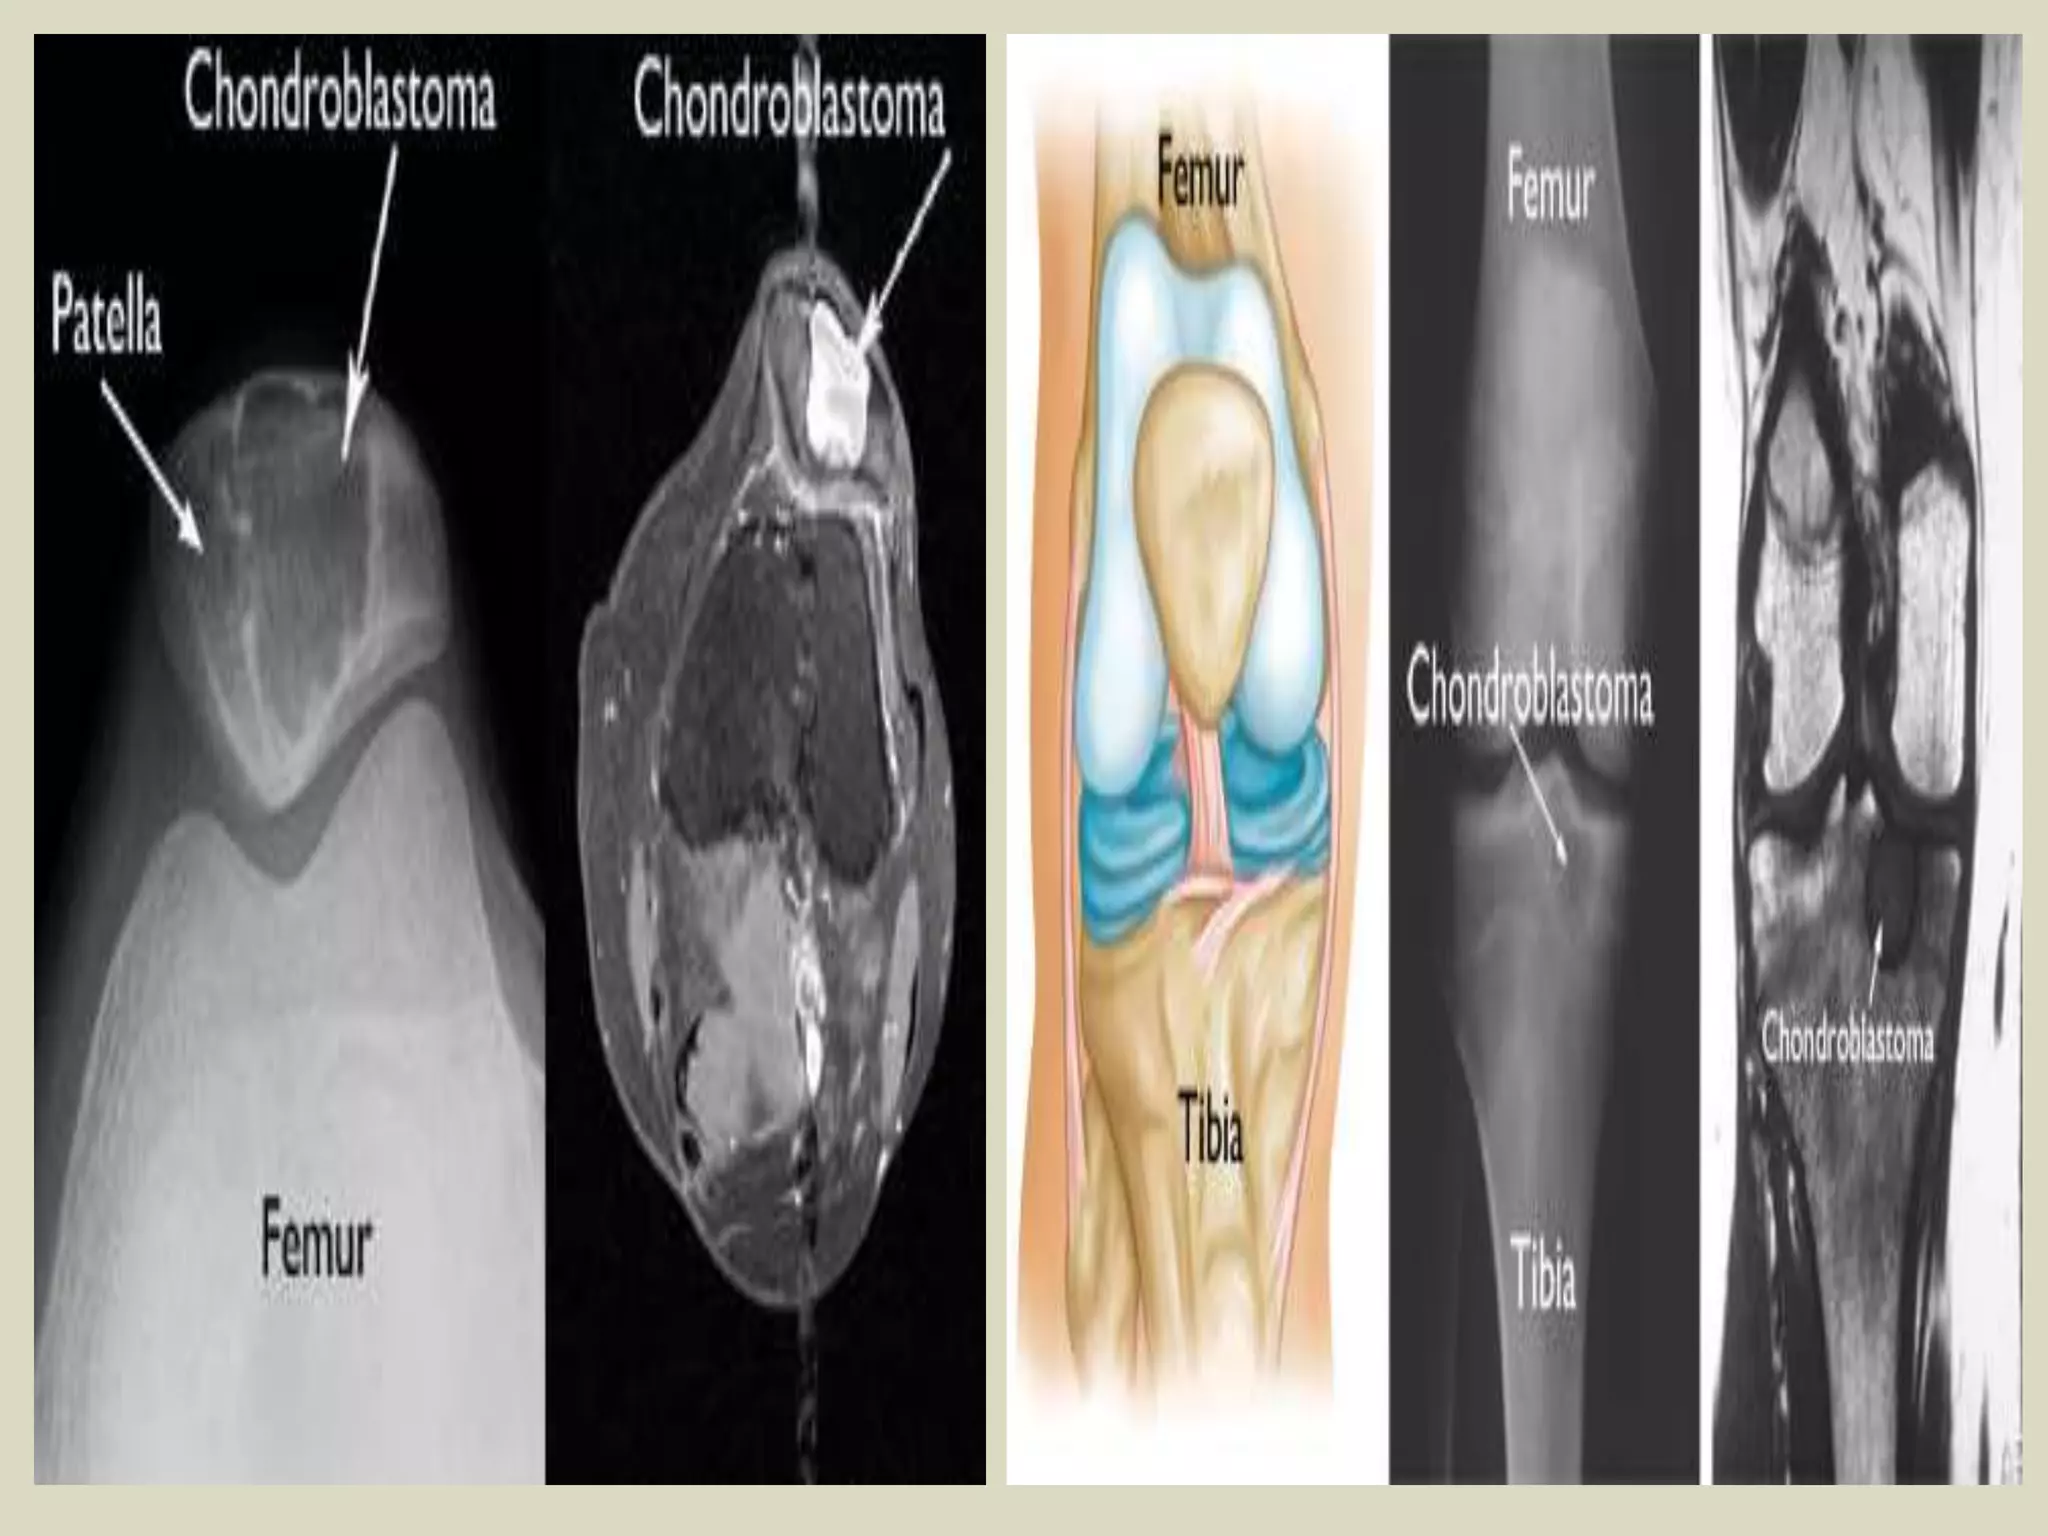

CHONDROBLASTOMA

Definition:

- Benign, cartilage producing neoplasm usually arising in the epiphyses of skeletally immature patients.

Epidemiology:

- Accounts for less than 1% of primary bone tumors.

- Most patients are between 10 and 25 years of age at diagnosis and there is a male predominance.

- Patients with skull and temporal bone involvement tend to present at an older age (40-50 years).

Sites of involvement:

- Usually arises in the epiphyses of the distal and proximal femur, followed by the proximal tibia

and proximal humerus.

- Patients with tumors arising in the flat bones, vertebrae and short tubular bones tend to be

older and skeletally mature, although rare cases have been reported in children.

Clinical findings:

- Majority of patients complain of localized pain, often mild, but sometimes of many years

duration.

- Soft tissue swelling, joint stiffness and limitation, and limp are reported less commonly.

- Minority of patients may develop joint effusion, especially around the knee.

Imaging:

- Typically lytic, centrally or eccentrically placed, relatively small lesions (3 to 6 cm), occupying

less than one half of the epiphysis.

- Shapely demarcated, with or without a thin sclerotic border.

- The presence of sclerotic rim, along with the younger age of the patient, helps to differentiate

chondroblastoma from giant cell tumor of bone, which generally lacks sclerotic border and occurs

in patients less than 20 years.

- Often helpful, matrix calcifications are only visible in about 1/3 of patients.

CHONDROBLASTOMA.

Chondroblastoma in the proximal tibia.